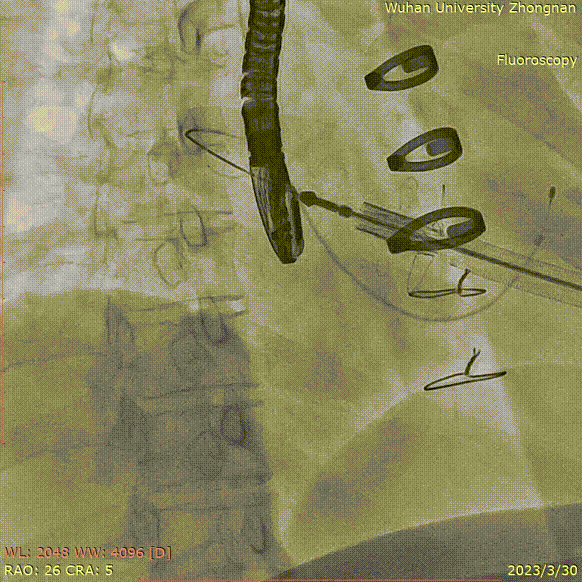

即刻行食道超声显示无瓣周漏:

三维食道超声显示瓣架展开呈圆形,形态满意: